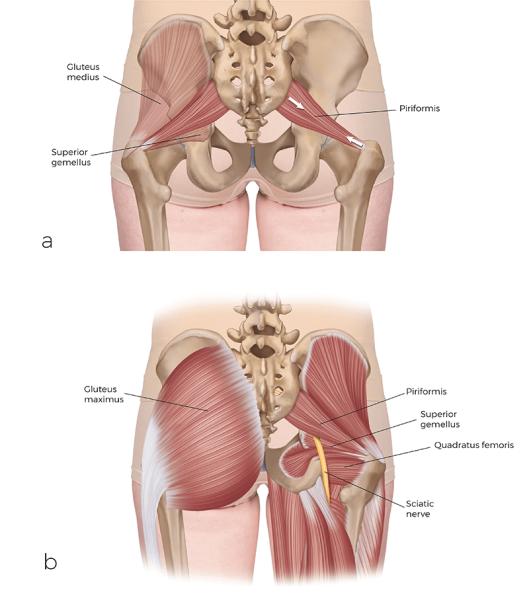

Let's start with one of the perennial favorites, the piriformis. What makes the piriformis cool? To begin, the piriformis is the only member of the deep lateral rotator muscle group (along with the superior and inferior gemellus, the obturator internus and externus, and the quadratus femoris) that also crosses the sacroiliac joint (SIJ), and therefore plays a role in SIJ function and dysfunction. In fact, it is often stated that the piriformis is the only muscle that directly crosses the SIJ. This is technically not true because the coccygeus and the superior deeper fibers of the gluteus maximus also cross the SIJ.

But the piriformis is likely the most important of these muscles, and it is incredibly important for stabilization of the SIJ. As a result, the piriformis is often overused and tight when there is SIJ dysfunction; and similarly, when the piriformis becomes tight, it can then lead to hypomobility dysfunction of the SIJ.

The piriformis has another feature that makes it stand out. The sciatic nerve emerges from the internal pelvis through the greater sciatic foramen between the piriformis and superior gemellus into the gluteal region. However, there is a common anomaly in which all, or part, of the sciatic nerve (usually the common fibular nerve portion) emerges either through the belly of the piriformis or superior to the piriformis. The common narrative is that this anomaly can lead to compression of the sciatic nerve, causing sciatica, mimicking sciatic nerve compression by a pathologic disc. However, it would seem likely that a tight piriformis could cause sciatic nerve compression, regardless of whether there is a normal presentation of the nerve or the anomalous presentation.